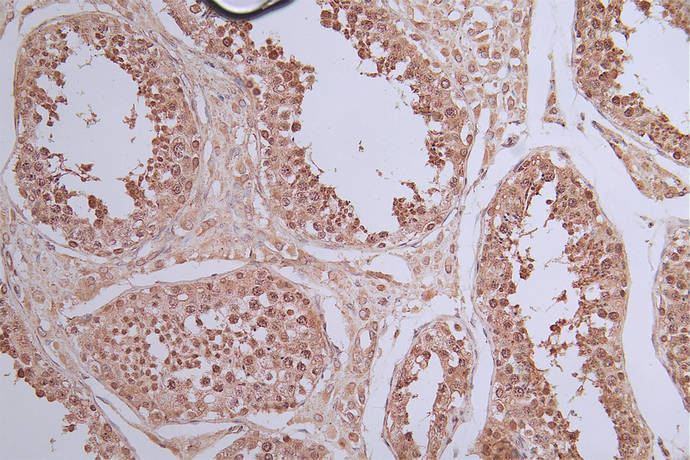

IHC image of CSB-RA989713A0HU diluted at 1:50 and staining in paraffin-embedded human testis tissue performed on a Leica BondTM system. After dewaxing and hydration, antigen retrieval was mediated by high pressure in a citrate buffer (pH 6.0). Section was blocked with 10% normal goat serum 30min at RT. Then primary antibody (1% BSA) was incubated at 4°C overnight. The primary is detected by a Goat anti-rabbit polymer IgG labeled by HRP and visualized using 0.40% DAB.